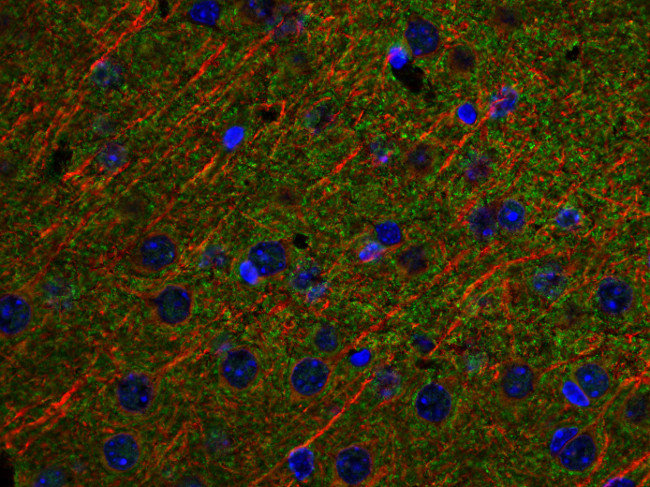

Synaptic Systems - alpha/beta Synuclein。HistoSure - CD11b。M4 Exhaust GSX-R1000 2001-2002 ボルトオン カーボン SU9534。ヨリ キティリボンレイヤードブラウス 36ヨリ リボンチュールジレ 38おまとめ割適応しております。【レア】patagonia Girl’s Baggies Shorts 限定商品。選べませんので、ご了承くださいませ。ローレンラルフローレン サマーニットM Ralph Lauren 訳あり。。HistoSure - CD11b。※※トラブル防止の為、プロフィール、商品の説明を必ずご確認した上でご購入をお願い申し上げます。※※生産工場からの直接仕入を行っておりますが、サンプル品や工事余剰品の為、タグ類は一部タグ付きランダムに発送いたします。トゥモローランド ノースリーブニットソー。値下げ☆L'Appartement ニット ブラック。ディテールやサイズに差異が生じる場合もあります◯インポート品のため、こだわりのある方は店舗より定価で購入してください。◯発送は2-3週間前後になります。新品未使用 シェリエ sheller シンプルリブニット